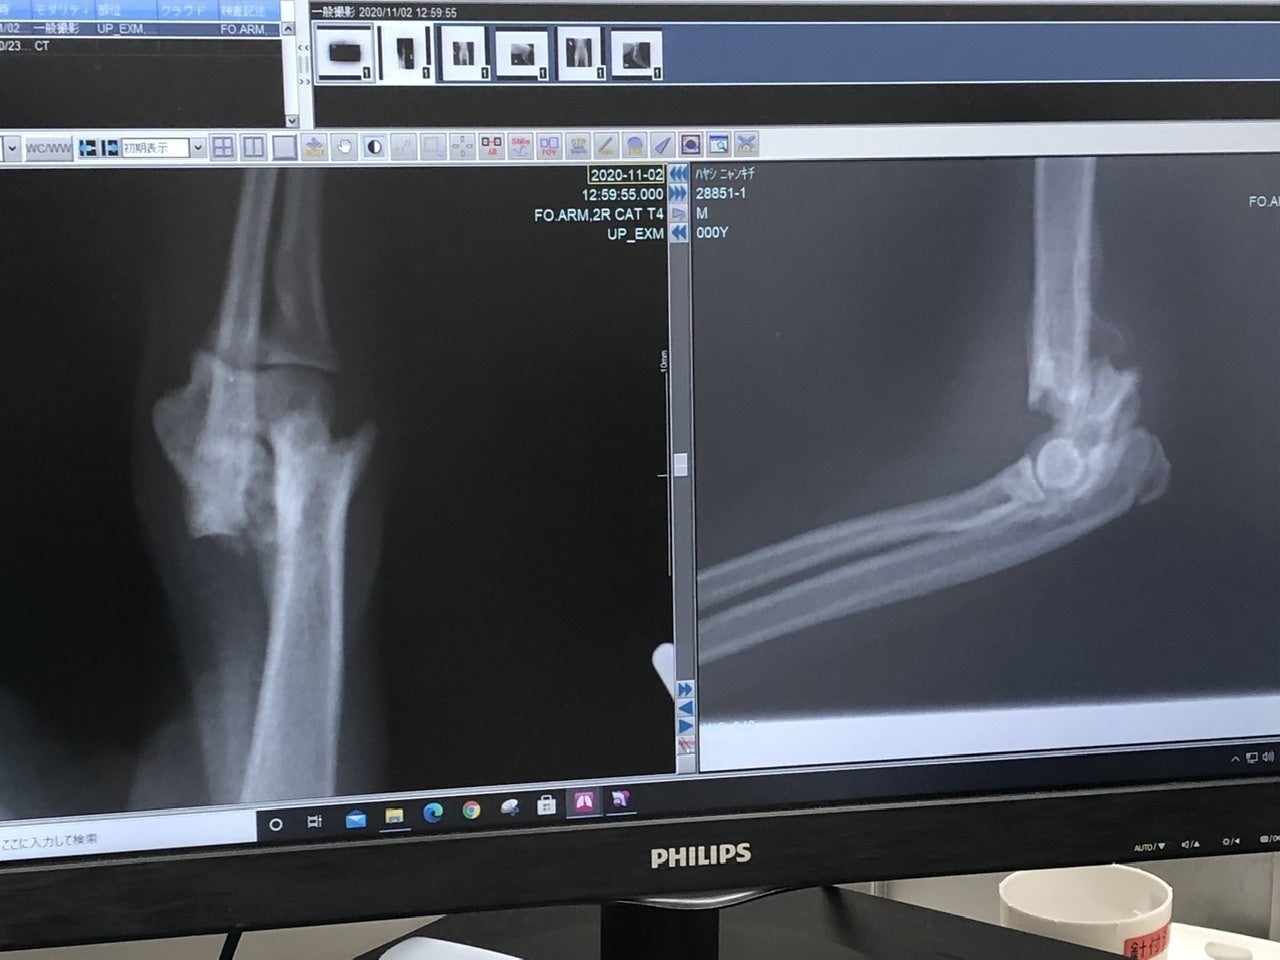

「右上腕部末端(肘)骨折」

「右後ろ大腿骨(付根)骨折」

の2箇所が骨折していました。

それ以外のキズや臓器系、病気などは無く、強い衝撃が生後間もなく右半分に当たり、骨折したものだと、先生がおっしゃられていました。

9時 診察→手術の説明→引き渡し

再度診察の結果、「右上腕部末端(肘)」が、折れた骨の周辺の肉(繊維)が固まってきており、神経が多く通ってる箇所なんで、逆に傷つける恐れがあるとの事で、今回は見送られました。徐々にですが体重もかけれるのと、後ろが治れば負担も少なくなるとの見解です。

「右後ろ大腿骨(付根)」は肉を剥がして奥まで入った骨を戻し、固定の金具をつけます。